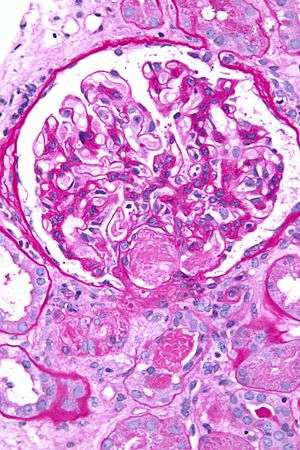

Glomerulus (kidney)

| Renal glomerulus | |

The glomerulus (red) within Bowman's capsule | |

A glomerulus (RP English pronunciation: /ɡlɒˈmɛr(j)uːləs/, American /ɡlɒˈmɛrələs/) is a network (as a tuft) of capillaries located at the beginning of a nephron in the kidney. It serves as the first stage in the filtering process of the blood carried out by the nephron in its formation of urine.

The glomerulus is surrounded by a cup-like sac known as Bowman's capsule. The blood plasma is filtered through the capillaries of the glomerulus into the capsule. The Bowman's capsule empties the filtrate into the proximal tubule that is also part of the duct system of the nephron.

A glomerulus and its surrounding Bowman's capsule constitute a renal corpuscle, the basic filtration unit of the kidney.[1] The rate at which blood is filtered through all of the glomeruli, and thus the measure of the overall renal function, is the glomerular filtration rate (GFR).

Glomerulus.